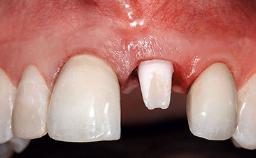

A 36-year-old male patient with a compromised maxillary central incisor was referred by his general dentist for consultation. The patient’s chief complaints were the gradual debonding of a temporary crown on the right central incisor and unsatisfactory esthetics due to an increasing diastema between the right central and lateral incisors. The patient reported a traumatic event some years previously, when a crown had been placed after root-canal treatment. The referring dentist wanted to provide a new crown restoration, but was concerned about the condition of the residual root. Anamnesis was negative for any other dental or periodontal pathology in the remaining dentition. The patient reported taking no medications: He was a smoker (10 to 15 cigs/day) and had realistic esthetic expectations.

Replacement of a Compromised Upper Right Central Incisor: Hard- and Soft-tissue Augmentation, Late Placement of an RC Bone Level Implant